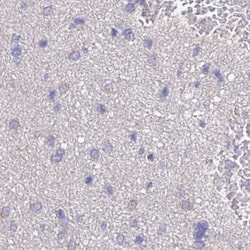

Invitrogen™ STIP1 Polyclonal Antibody

| Immunohistochemistry (Paraffin), Western Blot | |